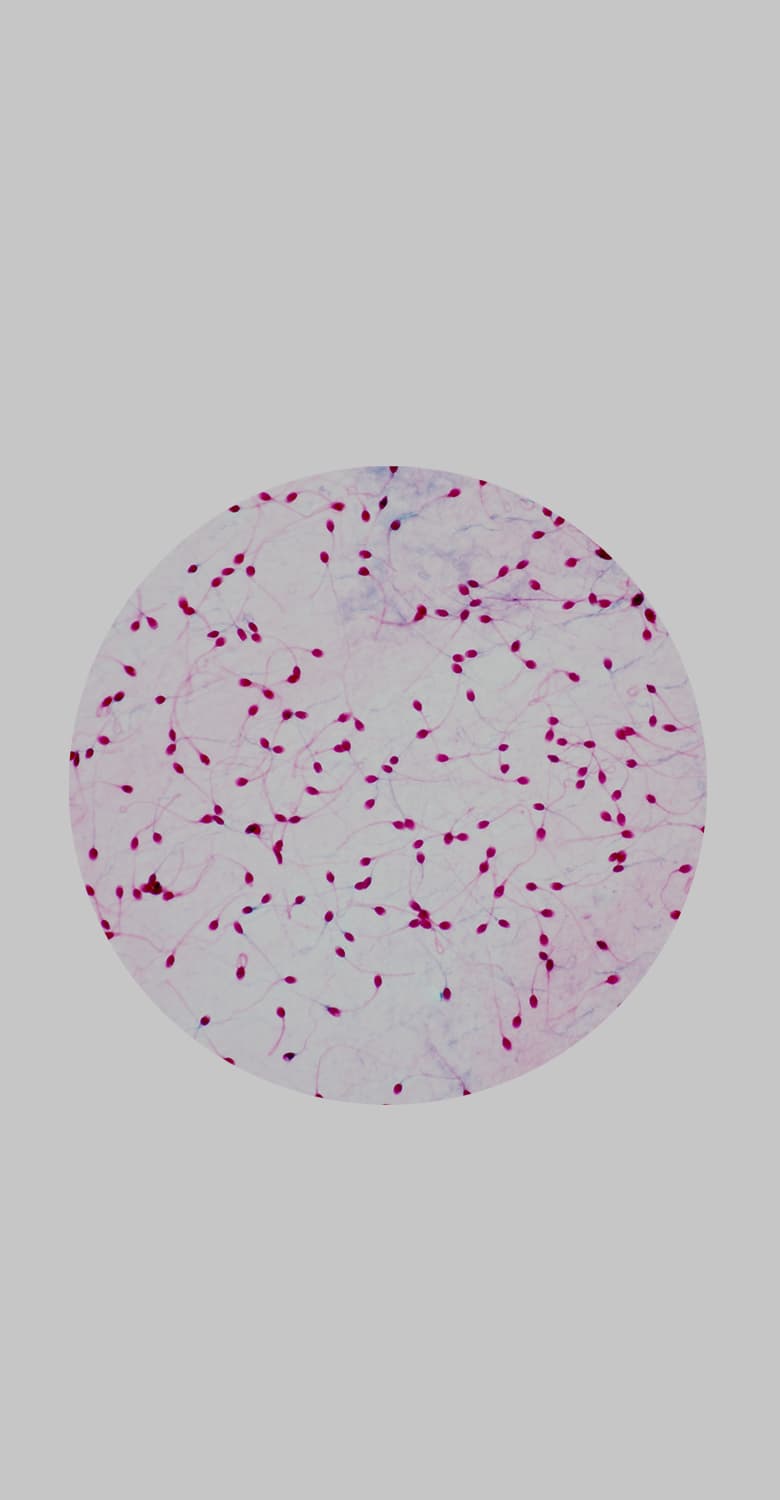

Спермограмма — это анализ спермы. С помощью данного анализа можно оценить функцию половых органов и проходимость семявыносящих путей, а также определиться с дальнейшей тактикой обследования. С ее помощью можно выявить отсутствие сперматозоидов в эякуляте, недостаточную подвижность и концентрацию, заподозрить воспалительные заболевания половых органов и так далее.

Базовый анализ эякулята (спермограмма) учитывает важные параметры эякулята: объем, вязкость, концентрацию сперматозоидов, их подвижность и морфологию.